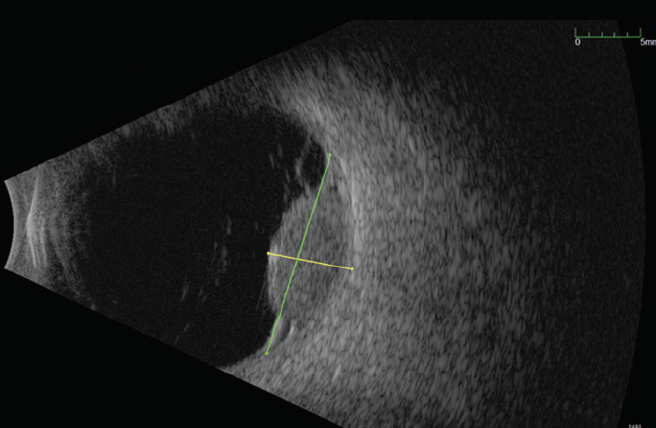

On examination, his VA was 20/70-1 OD and 20/20-1 in the left eye (OS). Anterior segment evaluation was normal. Posterior segment examination was notable for a temporal choroidal lesion OD. Fundus color photography documented an amelanotic choroidal lesion with elevation OD (Figure 1). Fluorescein angiography was initially interpreted as indicating choroidal melanoma: amelanotic pigmentation with intrinsic vascularity and hyperfluorescence with progressive leakage (Figure 2). B-scan ultrasound confirmed significant elevation of the retina and a large area of choroidal excavation measuring 15 mm by 16 mm by 6.7 mm (Figure 3).

<p>Figure 2. Fluorescein angiography shows leakage and hyperfluorescence surrounding the lesion.</p>

Figure 2. Fluorescein angiography shows leakage and hyperfluorescence surrounding the lesion.